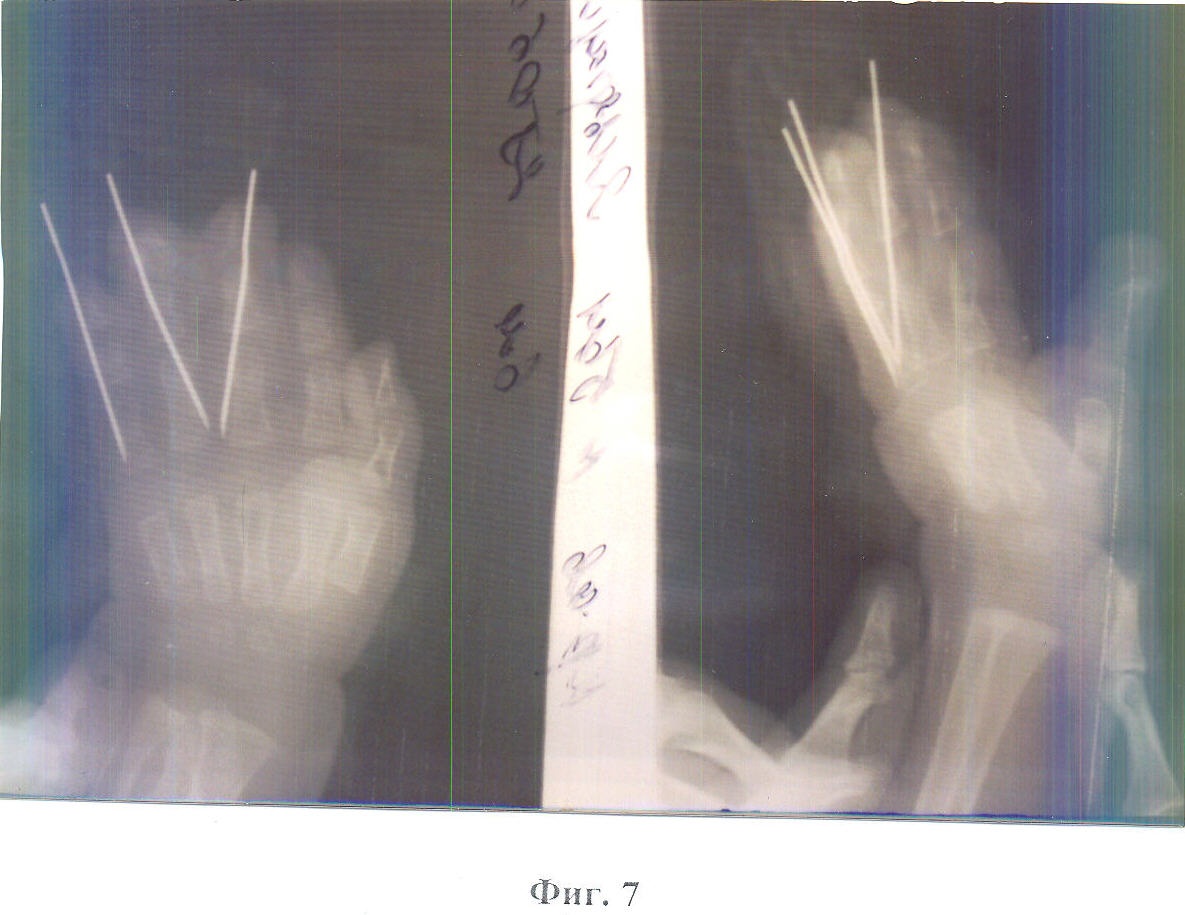

Способ поясняется фотографиями: на фиг.1 показан вид кисти до операции; на фиг.2 – рентгенограмма до операции; на фиг.3 – вид пальцев, разделенных до головок основных фаланг, со стороны ладони; на фиг.4 – вид разделенных пальцев со стороны тыла ладони; на фиг.5 – вид кисти после устранения деформации с фиксацией фаланг пальцев спицами; на фиг.6 – выкраивание полнослойного кожного лоскута на предплечье; на фиг.7 – рентгенограмма кисти после операции; на фиг.8 – вид кисти после операции. Способ осуществляется следующим образом.

После обработки операционного поля, под наркозом, производят рассечение кожи и подкожной клетчатки по тыльной поверхности сросшихся пальцев с разделением ногтевых пластин до костного сращения от их кончиков до головок основных фаланг. Далее, по ладонной поверхности производят линейный разрез от кончика пальца до головок основных фаланг в центральном направлении, после чего разделяют костный синостоз, разводят разделенные пальцы в стороны, устраняют сформировавшуюся деформацию до достижения нормальной анатомической оси и фиксируют фаланги этих пальцев тонкими спицами. При этом диаметр спиц должен быть наименьшим, с этой целью можно применять и инъекционные иглы. Для последующего закрытия образовавшихся дефектов боковых поверхностей разделенных пальцев на предплечье выкраивают полнослойный кожный лоскут, перфорируют и пришивают его к краям кожной раны разделенных пальцев. Асептическая повязка. Гипсовая лонгета.

Клинический пример: Ягф. А.А., дата рождения 27.11.2006. Поступила на лечение 18.06.2007. История болезни 3159. После предварительной подготовки больной под наркозом произвели рассечение кожи и подкожной клетчатки по тыльной поверхности пальцев с разделением ногтевых пластин. После этого по ладонной поверхности произвели линейный разрез от кончика пальца до головок основных фаланг в проксимальном направлении. Далее разделили костный синостоз, развели разделенные пальцы в стороны, устранили сформировавшуюся деформацию до достижения нормальной анатомической оси и зафиксировали фаланги этих пальцев тонкими инъекционными иглами. Для последующего закрытия образовавшихся дефектов боковых поверхностей разделенных пальцев на предплечье выкроили полнослойный кожный лоскут, произвели его перфорацию и пришили к краям кожной раны разделенных пальцев. Наложили асептическую повязку и гипсовую лонгету.